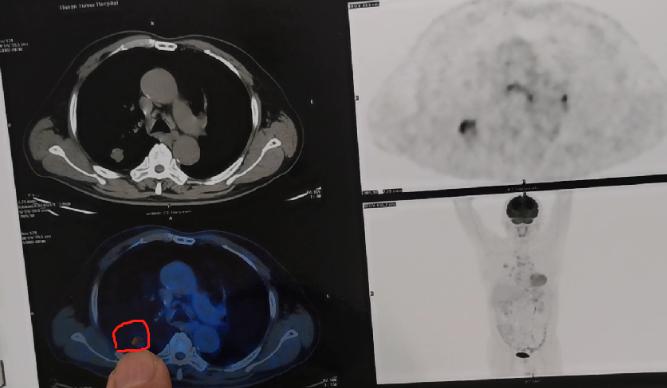

河南那15岁男孩直肠癌晚期, 肝上全是肿瘤,看完真揪心! 医生一问病因, 在外打工的爸妈啥都不知道! 他们总觉得亏欠孩子,就一个劲打钱,以为给钱就是疼他,可这“补偿”竟把孩子喂进了绝境! 孩子揣着钱,哪会按时吃热饭? 顿顿泡面、火腿肠配可乐,父母以为的“爱”,早变成了催命的“毒药”。 等肚子疼到扛不住,诊断书下来才傻眼,这哪是小毛病? 是父母用“给钱”代替陪伴,用“愧疚”掩盖管教埋下的祸根。 孩子要的从不是兜里的钱,是饭桌上的唠叨、是被管着说“不许吃垃圾食品”的在意。 要是你在外打工,会咋平衡给孩子的钱和实打实的关心呢?